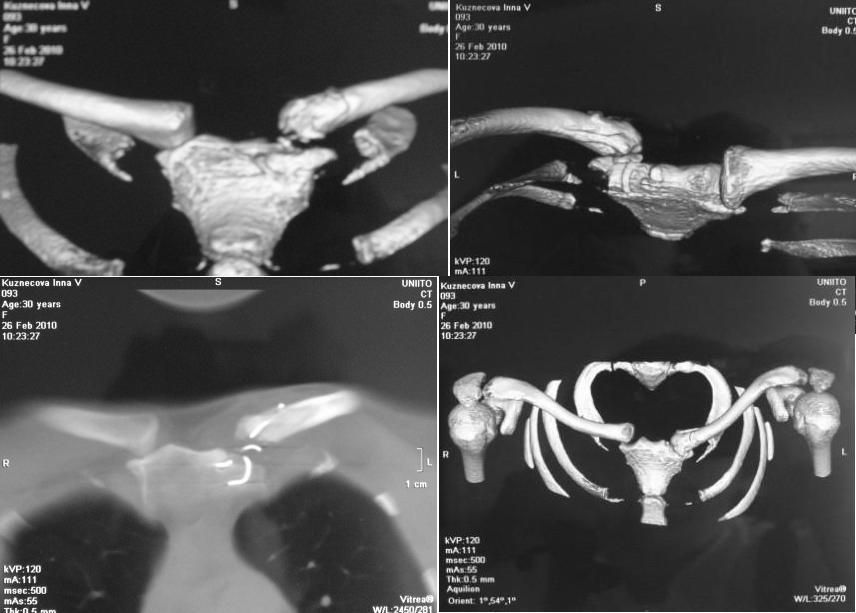

20.07.09г. шов лавсаном с фиксацией 8-образной ватно-марлевой повязкой с рецидивом вывиха грудинного конца ключицы;в сентябре 2009г. повторный шов лавсаном с фиксацией 8-образной ватно-марлевой повязкой с рецидивом вывиха грудинного конца ключицы,в ноябре 2009г. остеосинтез проволочной петлей и фиксацией торакобрахиальной гипсовой повязкой с последующим разрывом проволоки и рецидивом вывиха грудинного конца ключицы.29.12.09г. была выписана к труду. Работа пациентки связана с физическими нагрузками. В настоящее время предъявляет жалобы на деформацию и появление болей при движениях руки в грудино-ключичном сочленении слева. Локально: левое надплечье укорочено. Имеется выстояние грудинного конца ключицы кпереди и кнутри, которое при движении руки увеличивается и при этом появляется болезненность и хруст в грудино-ключичном сочленении слева. Пальпация грудино-ключичного сочленения безболезненная. Движения в левом плечевом суставе не ограниченные. Мышечная сила сохранная. Сосудистых и чувствительных расстройств нет.Диагноз: застарелый передневнутренний подвывих грудинного конца левой ключицы. Сросшийся перелом грудинного конца левой ключицы. Частичный дефект суставного конца левой ключицы.На КТ от 26.02.10г. диастаз между суставной поверхностью грудины и левой ключицей составляет 0,8-0,9см. Вопросы: Есть ли необходимость в оперативном вмешательстве?Вид хирургического пособия?Фиксация?